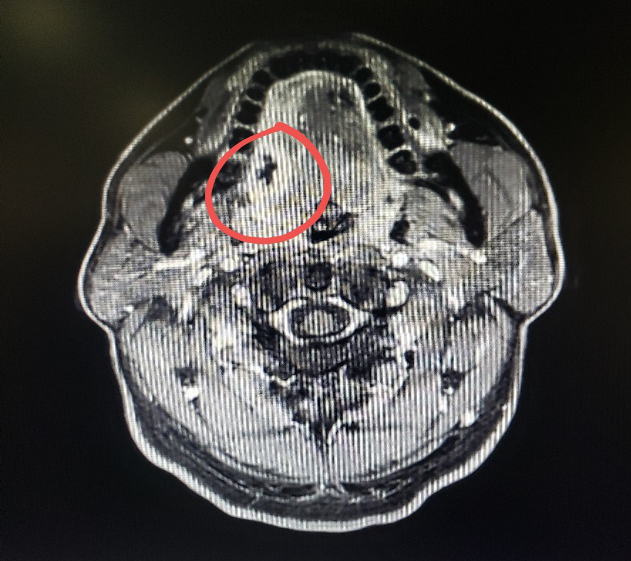

图二:病人的术前MRI

图三:病人的术前MRI

图四:病人的术前MRI

那么这个异物包裹性脓肿里面到底是什么呢?我猜测要不是鸡骨,要不就是鱼刺,但鸡骨的话体积比较大,在CT上一般能看得出来,而且这么大的鸡骨插进舌头,病人的症状会非常明显,不会等到几个月后才来就诊。而鱼骨一般是很纤细的,在CT上是看不出来的,不过我们仔细看影像的话,还是可以在切面上发现小的阻射影的。